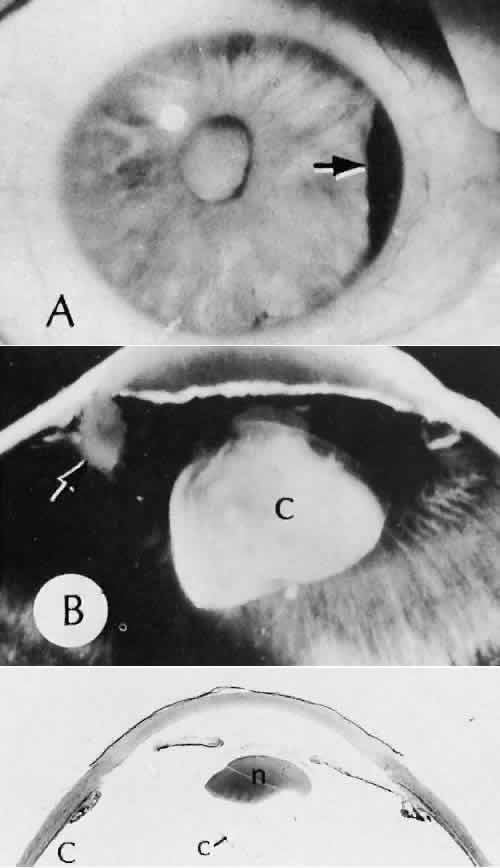

Cyclocryotherapy, cyclodiathermy (Fig. 20), and therapeutic ultrasonography apply energy directly to the pars plicata and cause lysis of the ciliary muscle and occlusion of the vascular supply, leading to extensive necrosis and scarring. Pressure lowering is accomplished by a reduction of aqueous production. Heat applied to the sclera may cause necrosis and localized scleral thinning. Cold applied to the sclera, unless extreme, does not cause any clinical or histologic changes.

Fig. 20. Cyclodiathermy treatment of the ciliary body to control glaucoma. A. Gross photograph illustrates extensive areas of depigmentation mainly in the region of the pars plana (arrows) rather than the pars plicata. B. Light micrograph of the region of the pars plana illustrates an extensive area of tissue degeneration of the pars plana (between arrows) in the late postoperative course. C. Light micrograph of the destructive effects of cyclocryotherapy also in the region of the pars plana and pars plicata. The ciliary epithelium in the early postoperative period is necrotic and cystic. (Hematoxin-eosin stain; A, × 8; B, × 16.)